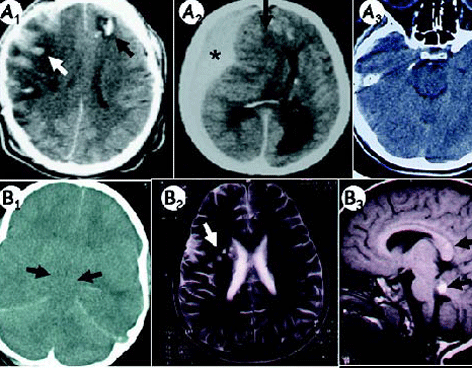

Las Palmas, España.- Una neuropsicóloga española demostró que las últimas técnicas de neuroimagen permiten "ver" respuestas cerebrales a estímulos en pacientes que evolucionan de un estado de coma a otro vegetativo, lo que podría mejorar su diagnóstico, desarrollar un tratamiento y predecir su recuperación.

Fernández Espejo ha tratado con estas técnicas de neuroimagen de última generación, como la resonancia magnética funcional, a 460 pacientes, tanto en Barcelona como en Bélgica, el Reino Unido y Canadá, donde trabaja desde hace un año.

Para ello, Fernández demostró que estimulando a este tipo de pacientes con narraciones simples y estímulos visuales se puede comprobar si su cerebro responde de la misma forma que lo haría el de una persona sana y, con ello, confirmar que determinadas redes cerebrales "estarán preservadas".

Fernández Espejo, de 32 años, explicó hoy que estas técnicas permiten evaluar a un nivel muy preciso cambios sutiles en el cerebro del paciente y, por tanto, estimar el nivel de daño que sufre, lo que permitiría predecir "si es posible una recuperación", indicó.

Por eso, destacó que estas técnicas de imagen cerebral "permiten ir más allá de lo que el paciente muestra a nivel externo para ver si su cerebro responde de una manera similar a la de una persona sana".